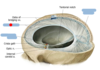

Identify the blue boxes.

- dura mater (meningeal and periosteal layers)

- falx cerebri

- emissary vein